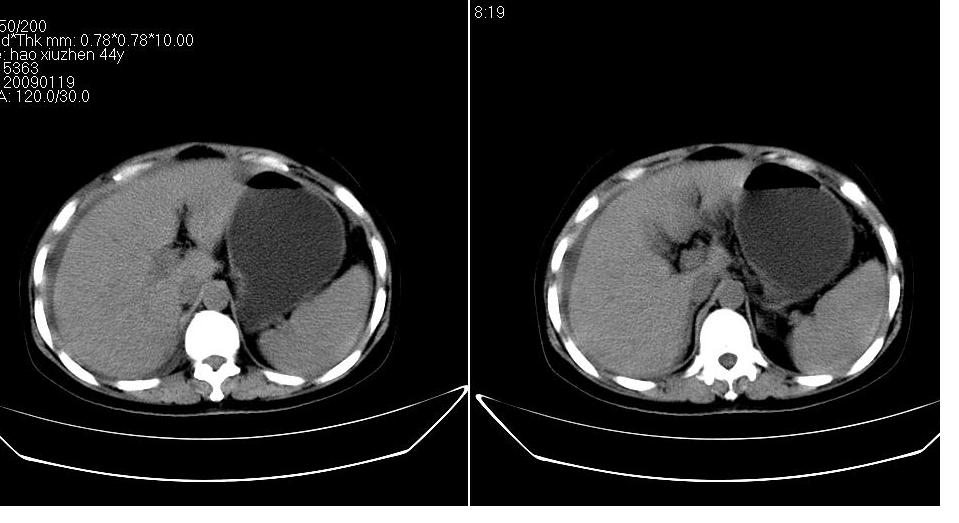

以下是引用zbp537在2009-1-19 14:09:00的发言:[br]从这个平扫图像上看,只能考虑:1、胸腹水。2、脾脏包膜下弧形高密度影,疑出血,建议复查。[br]既然腹水中有恶性细胞,建议行腹部ct增强扫描及胸部扫描。

以下是引用随光逐影在2009-1-19 15:47:00的发言:[br]1)不排除胃癌可能;建议行胃镜检查。2)腹水。3)右侧胸腔积液。

以下是引用jiangjing在2009-1-19 18:21:00的发言:[br]1 网膜污垢征---肿瘤网膜转移.2)腹水。3)右侧胸腔积液